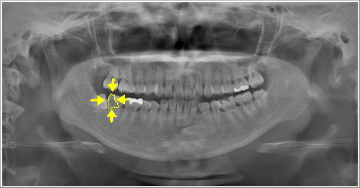

親知らずは虫歯にならず、その前の歯だけに大きな虫歯を造っている親知らずもあります。

また、一見それほど大きな虫歯ではない様に見える歯でも、少し顔を出した親知らずの為に抜かなければならぬ程の大きな虫歯になっている事もあるのです。

大切な歯を守る為に親知らずが顔を出したら一度歯科医院で調べてみてはいかがでしょう?